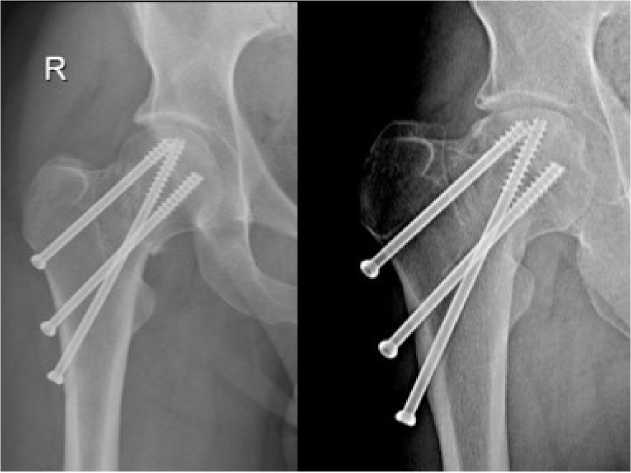

Как видно из таблицы, метод BDSF обеспечил достоверно более высокую частоту сращения переломов, более короткие сроки консолидации, а также значимо реже приводил к вторичным деформациям – укорочению шейки и варусному коллапсу (рис. 2).

Рисунок 2. Сросшийся перелом шейки бедренной кости на фоне остеосинтеза

Figure 2. Healed fracture of the femoral neck with osteosynthesis

В группе BDSF отсутствие консолидации было отмечено у 4 (10,6%) пациентов: в 2-х (5,2%) случаях сформировался ложный сустав, ещё в 2-х (5,2%) причиной несращения стал АНГБК. Во 2-й группе несращение произошло у 10 (25%) пациентов (p=0,003 по сравнению с гр. 1): ложный сустав – 3 (7,5%) случая, АНГБК – 7 (17,5%) случаев. Таким образом, частота развития АНГБК была достоверно ниже при использовании метода BDSF (p=0,001). (табл. 2). Случаев подвертельных переломов не было зафиксировано ни в одной группе. Всем пациентам с несращением и АНГБК было выполнено тотальное эндопротезирование тазобедренного сустава.